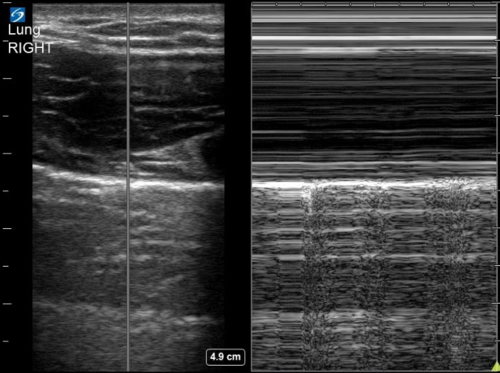

A pneumothorax separates the visceral and parietal pleura, eliminating normal lung sliding between these layers on lung us. Once you understand these basic lung ultrasound findings you will be able to interpret just about any lung ultrasound images. When m mode is used on a normal lung, the lung (and the air inside it) moves back and forth across this single ultrasound beam creating a picture that is often compared to a sandy beach. Unless the pneumothorax is loculated or there are adhesions, the gas moves freely within the thoracic cavity. There is normal lung sliding on the right side. Lung ultrasound pathology profiles such as pneumothorax, pneumonia, cardiogenic pulmonary edema, etc will have a different combination and distribution of these pathological lung ultrasound findings/signs. Nov 08, 2017 · primary spontaneous pneumothorax: 3 article feature images from this case Ein pneumothorax (gelber pfeil) mit noch geringer. To evaluate for pneumothorax with ultrasound, have the patient lay supine. In the supine trauma patient, this will typically be the anterior chest wall lateral to the sternum in the second intercostal space. Among 302 analyzable controls, 65 had absent lung sliding, 16 of them showed an a line sign, and none showed a lung point. Each site was scanned twice at each time point.

Ruling out a pneumothorax is the easy part for me, and it doesn't require much more than a quick visual inspection. Ultrasound can also allow semiquantitative assessment of pneumothorax size by assessing the position of the lung point. Once you understand these basic lung ultrasound findings you will be able to interpret just about any lung ultrasound images. · february 14, 2020 · 1 min read. Nov 08, 2017 · primary spontaneous pneumothorax: Ultrasound use may therefore obviate the need for ct in a majority of cases. Additionally, it can result in timely diagnoses specifically in neonatal pneumothorax. The probe should be oriented perpendicular to the ribs (usually marker dot towards the head). You can also use m mode, or motion mode, which provides an image showing tissue motion along a single ultrasound beam. Unless the pneumothorax is loculated or there are adhesions, the gas moves freely within the thoracic cavity. At its heart, the concept behind using ultrasound to evaluate for air in the space between the visceral and parietal pleura is straightforward. Ultrasound scans in all 43 examinable patients with pneumothorax showed absent lung sliding, 41 of 43 patients had the a line sign, and 34 exhibited a lung point. Ultrasound outperforms cxr in evaluation of pneumothorax in blunt trauma patients, but there cite this article as:

Nov 08, 2017 · primary spontaneous pneumothorax: Ultrasound outperforms cxr in evaluation of pneumothorax in blunt trauma patients, but there cite this article as: Lack of ionizing radiation and easy operation are benefits of this imaging technique. 1 traumatic pneumothorax is common in dogs, whereas spontaneous pneumothorax is relatively rare. In the supine trauma patient, this will typically be the anterior chest wall lateral to the sternum in the second intercostal space. When m mode is used on a normal lung, the lung (and the air inside it) moves back and forth across this single ultrasound beam creating a picture that is often compared to a sandy beach. To evaluate for pneumothorax with ultrasound, have the patient lay supine. A pneumothorax separates the visceral and parietal pleura, eliminating normal lung sliding between these layers on lung us. Among 302 analyzable controls, 65 had absent lung sliding, 16 of them showed an a line sign, and none showed a lung point. Since then there have been many studies that have shown bedside ultrasound can rapidly detect pneumothorax, helping avoid serious potential consequences (i.e. These are the thoracic radiographs: Thoracic ultrasound has more sensitivity than a supine chest radiograph (see: Identification of a lung point on lung us yields 100% specificity for pneumothorax (58).